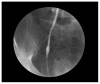

A male, 32 years of age, presented with dysuria and abdominal pain, but no gross hematuria. He emigrated three years earlier from Somalia, East Africa, and was currently employed as a poultry processor in a rural Wisconsin community. The patient denied any trauma, sexual activity, or family history of significant illness. Abdominal and genitourinary exams were normal with negative tests for gonococcus and chlamydia. Urinalysis demonstrated microhematuria. A urogram and retrograde pyelogram revealed a mildly dilated right ureter down to the ureterovesical junction. Cystoscopy showed punctate white lesions on the bladder urothelium. Ureteroscopy was used to biopsy abnormal tissue in the distal ureter and bladder. Biopsy tissue demonstrated deposits of Schistosoma haematobium eggs. No ova were seen in collected urine specimens. The patient was successfully treated with praziquantel and will be monitored for sequelae of the disease. Schistosomiasis (Bilharziasis) can be expected to be seen with increasing frequency in the United States with the continuing influx of immigrants and refugees, as well as the return of travelers and soldiers from endemic areas. While no intermediate snail host exists for the transmission of Schistosoma sp. in the United States, the continued importation of exotic animals including snails from Africa, as well as the ability of schistosomes to shift host species warrants concern. Additionally, increasing disease associated with non-human bird schistosomes of the same genus seen in the midwestern United States is occurring throughout Europe. One should be aware that praziquantel may not always be available or effective in the treatment of schistosomiasis. It behooves the practicing clinician to remain updated on the status of this widespread zoonosis.